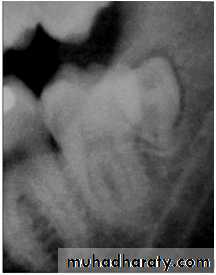

Paramolar blocking the eruption of 3rd molar.

MesiodensDistomolars(4th molar)

Distodens or distomolarParamolar